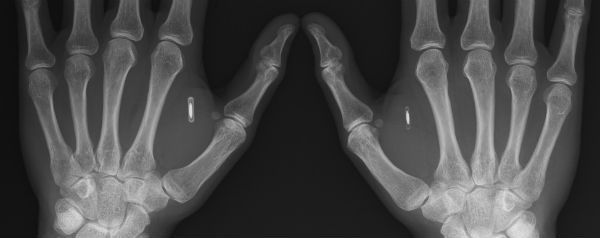

Cyborg Amal Graafstra hoeft maar met zijn handchip te zwaaien en zijn motor start.

Vijf zintuigen is mooi, maar zes of zeven is nog mooier. Dat vindt Amal Graafstra. In 2005 bouwde hij voor het eerst een radiochip in zijn hand. De deur viel steeds achter hem dicht als hij een computer naar binnen wilde dragen op zijn kantoortje in Seattle. Lastig. De twee zendertjes die Graafstra nu in zijn hand heeft, openen niet alleen deuren, ze melden hem ook vanzelf aan als hij achter zijn computer gaat zitten of zijn smartphone oppakt.

Amal Graafstra“De tags in mijn hand voelen eigenlijk wel prettig aan”, mailt Graafstra. “En

het leuke is dat ik ze kan gebruiken voor allerlei nieuwe projecten. Ik hoef tegenwoordig maar met mijn hand te zwaaien om mijn motor te starten.”